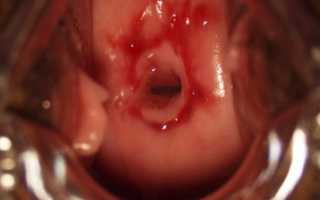

Цервикальная дисплазия

Часто дисплазию путают с цервикальной эрозией, для которой характерно механическое повреждение клеток эпителия. При цервикальной дисплазии клетки видоизменяются, как правило не затрагивая верхний шар и его оболочку. Правильная и своевременная диагностика является залогом эффективности лечения недуга.